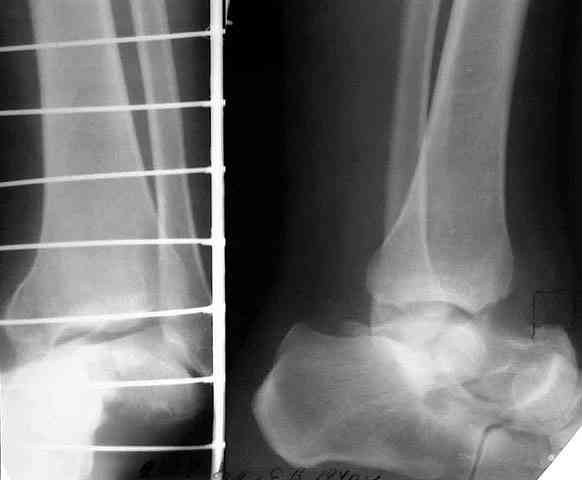

> кости. Выполнена ПХО, фиксация голени и стопы стержневым аппаратом.

> В качестве варианта хирургического лечения мы считаем возможным

> выполнить следующее вмешательство: артродез большеберцовой и

> пяточной костей

> в сочетании с артродезом переднего края большеберцовой кости и

> головки таранной кости с фиксацией спонгиозными винтами.

Специально за этим гнаться не приходится. Обычно передний край большеберцовой кости хорошо прилегает к культе тарана, подравнять поверхности для лучшего контакта - не проблема. Наоборот, как бы слишком много от шейки тарана не оставить. Если сделать полную астрагалэктомию, то есть не оставлять и головку тарана - тоже беда небольшая.

Если есть целые ПК и ТЛ суставы, то для нормальной опороспособности достаточно позаботиться только берцово-пяточном блоке.

Учитывая ликвидацию голеностопного и подтаранного суставов, надо поберечь остающиеся, чтобы рессорную функцию стопы сохранить по максимуму. Поэтому лучше избегать всякого рода дополнительных вмешательств поблизости от ТЛ и ПК суставов, а то на некоторых схемах чуть ли не их замыкание предусматривается. Опил большеберцовой кости

нарисован слишком горизонтальный, надо пересекать ее параллельно контактной поверхности пятки, наклонно, т.е. больше убрать сзади.